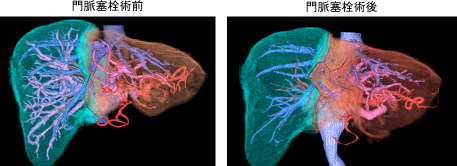

VINCAT™で肝両葉に5個の大腸癌肝転移を認めた、導入化学療法後に紹介となりました。

2ヵ所に分けて肝切除を行いました。根治的な切除が可能でした(手術時間 6時間、出血量 100ml)。

2ヶ月後に腹腔鏡下低位前方切除術を行いました。(出血量 100ml)

肝切除後1年半後に単発の肺転移を認めました。3ヶ月観察を行い、手術を行いました。

胸腔鏡補助下に肺部分切除術を行いました(出血量200ml)。

左が胸腔鏡所見、右が切除標本を示す。3回の手術の術中出血量はすべて100ml以下でした。